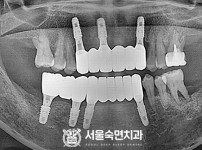

임플란트-전후사진3

치과를-선택할-때-꼭-확인하세요-서울숙면치과-임플란트-전후사진